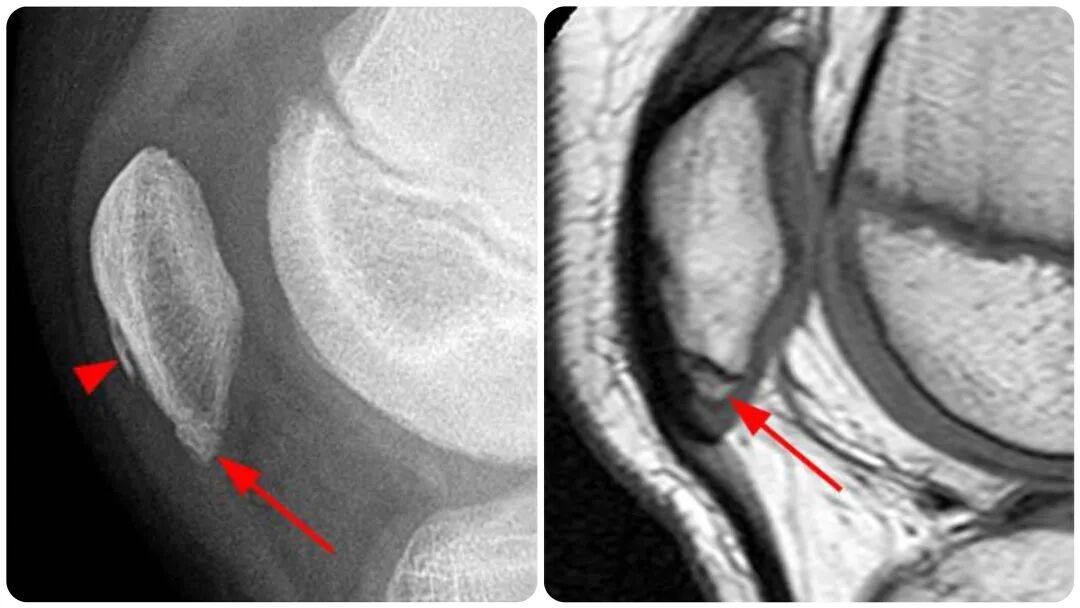

图3 髌骨下极存在撕脱性骨折(长箭头所示)。可见轻度软组织肿胀。髌骨前方的高密度影是一个骨化中心(箭头端所示)。

Sinding-Larsen-Johansson 病的影像学表现包括在髌骨下缘出现副骨化中心或撕脱骨片,并伴有软组织肿胀(图3)。其在X线片和磁共振成像(MRI)上的表现基本上与髌骨袖套状骨折难以区分,鉴别诊断依赖于临床病史和体格检查。

图5:(1a)侧位X线片和(1b)T1加权矢状位图像上显示的髌骨下极正常骨化中心(箭头所示)。同时需注意,在髌骨前表面存在正常的不规则骨化(箭头端所示),在平片上显示得最为清晰。该患者的T2加权图像未显示出提示创伤病因的水肿情况。